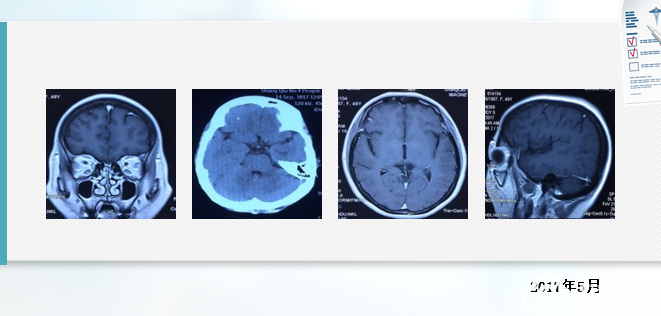

2018年5月16日,确诊腺癌18个月,出现头疼,纳差,呕吐10天,大小便失禁1天,再次入院,查体意识模糊、嗜睡状态,四肢机体不能配合。

经治疗17个月后,脑转移加重,疾病进展,考虑耐药。

p右上肺腺癌 cT2N3M1 IV期 EGFR突变型

脑部多发结节,脑转移

双肺、骨转移靶向治疗17个月后进展

T790M阳性

2018年5月22日 口服奥希替尼 80mg qd降颅压,应用激素及对症支持治疗 唑来膦酸 4mg q28天

2018年5月22日,服药第二天,神志转轻、呕吐停止,头疼明显减轻,能进食,第三天可下床活动。

2018年6月1日出院。